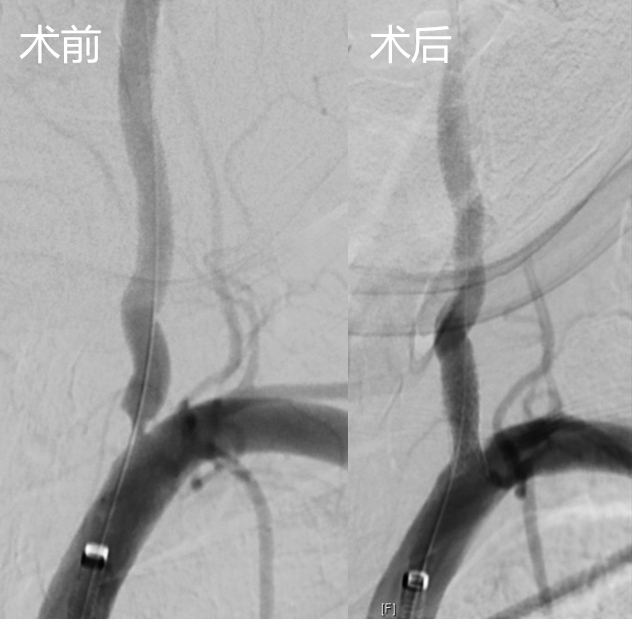

入院后,医师仔细检查发现柳伯伯属于左侧椎动脉起始段狭窄。柳伯伯先天右侧椎动脉狭窄,全靠优势的左侧椎动脉后循环,左侧的狭窄造成了2年来频繁的后循环缺血发作。在血管外科行支架治疗之后,柳伯伯头晕症状消失,顺利出院。

但是如果椎动脉起始处已经出现狭窄,就需要借助药物治疗、外科治疗、介入治疗。药物治疗以抗血小板治疗为主,结合降压、降脂以及降糖药物的治疗,可以延缓动脉硬化狭窄闭塞的发展,目前还没有一种药物能够消除动脉斑块。对重度椎动脉起始处狭窄或有“预警”信号的有症状椎动脉起始处狭窄患者,椎动脉起始处支架植入术是首选治疗方案,有经验的血管外科医师可以娴熟地胜任该项手术,该技术创伤小、恢复快、住院时间段的明显优势。